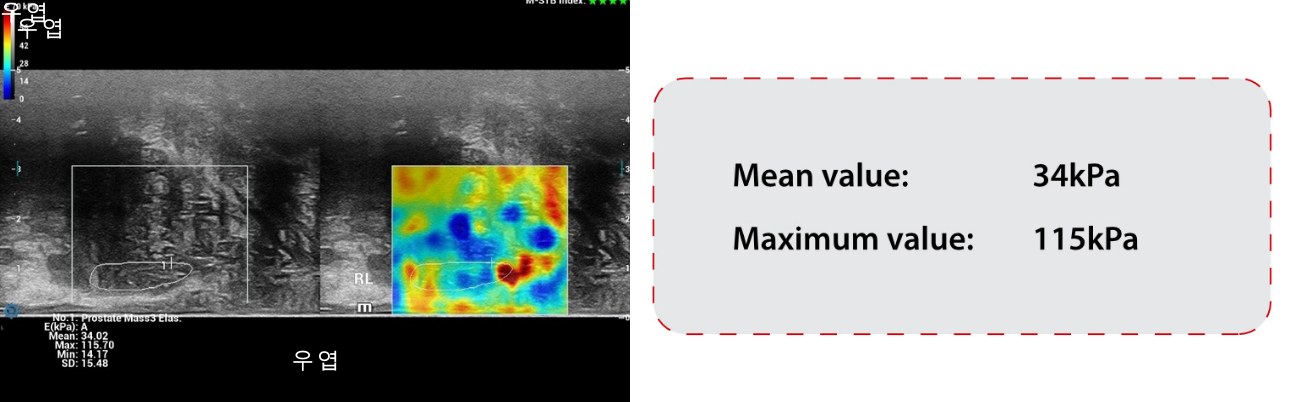

??? ?? ???(SWE) ??:

STESWE ŌĆō ??? ?? ???:

??? ?? ???(SWE)? ??? 34kPa, ??? 115kPa? ?? ??(??6). ?? ??? SWE? ???? ? ???? ? ??.(?? = 19 kPa, ?? = 36 kPa). (??7) ????? ??? ????(PZ)?? ???? ?? ???? ???. ????(TZ)? ??? ???? ?? ????(PZ)?? ? ???. ????(TZ)? ????(PZ)? ??? ???.

- STE? ??? ???? ???? ??????, ?? ???? 34kPa, ??????? 115kPa????.